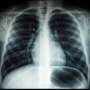

Lung cancer mortality rates among women in European Union (EU) countries are projected to stabilize by 2026, after a sustained increase spanning over 25 years. This trend marks a significant shift in the battle against a disease that has claimed countless lives across the continent, although Spain is noted as an exception to this forecast.

Data indicates that while overall lung cancer death rates among women have been on the rise, the anticipated plateau is based on current projections from various health organizations. According to the World Health Organization, lung cancer remains one of the leading causes of cancer-related deaths among women in the region.

The stabilization of lung cancer mortality rates is attributed to several factors, including improved screening practices, increased awareness of the risks associated with smoking, and advancements in treatment options. Countries that have implemented stringent anti-smoking legislation and public health campaigns have seen more significant declines in mortality rates.